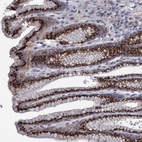

Immunohistochemical staining of human stomach shows strong dot like cytoplasmic positivity in glandular cells.